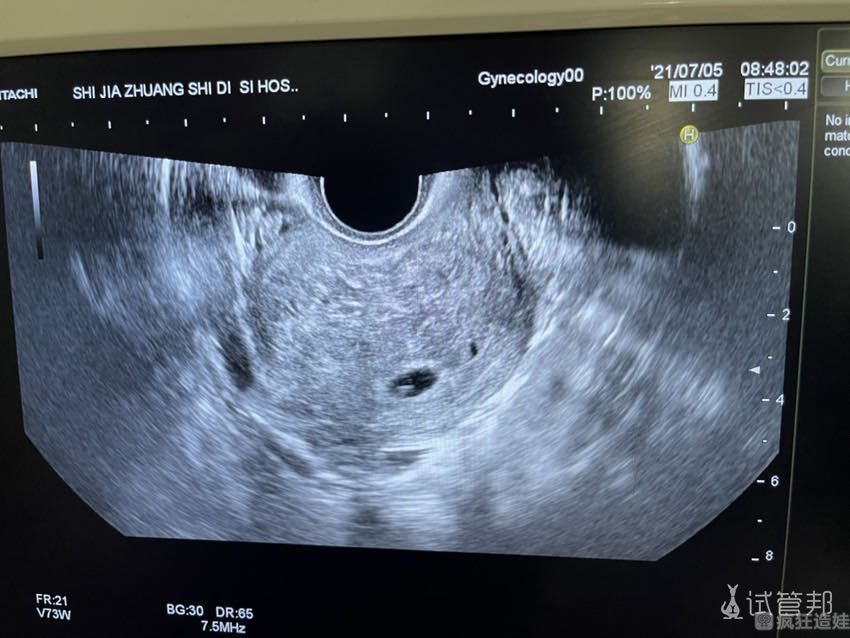

宝贝已经8w+了,下周就计划着去给宝贝做二超,但是自己心里还挺有底的,毕竟宝贝是从好几个胚里选出来的最健康的一个啦!当时吸引我去做二代试管婴儿的一大原因就是可以解决不孕不育困扰,在技术范围内给宝贝一个好的基础,趁着年轻生了宝宝自己的身体也能更快好孕。

还好我二代试管婴儿做的非常顺利,去医院做了一些前期身体检查后确认没什么问题后就开始根据医生定制的方案正式进周,没想到一促一移就成功了,试管少受罪感觉怀孕都更加容易些,当然也要感谢宝宝乖乖的抓住了我,更值得感谢的是福建医科大学附属第一医院全体医护人员的精心照料,不仅妙手还能仁心,真的觉得自己太幸运了!一直到现在准备二超都没再遇到什么困难,或许也是宝贝和我的缘分到了吧!